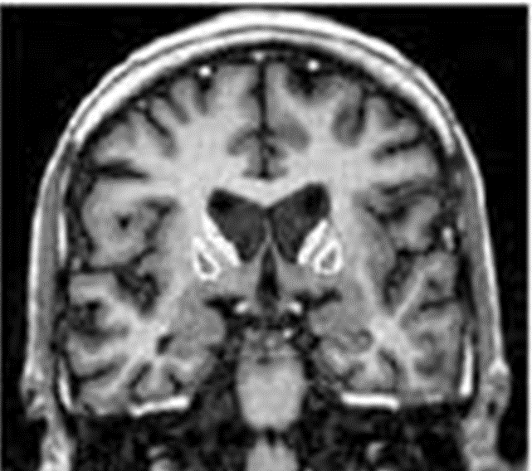

How would Huntington’s disease appear on imaging?

atrophy of cerebral cortex & caudate nucleus